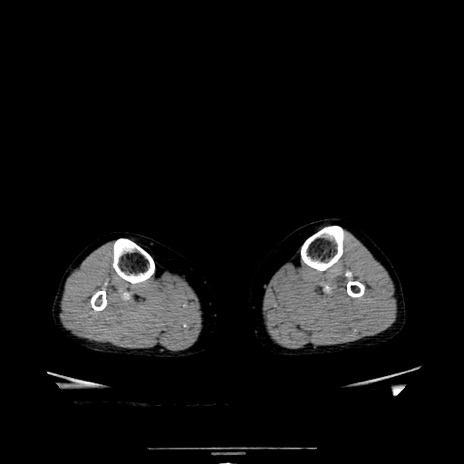

症例5(横断像)

【症例】70歳代女性

【主訴】お腹が張る

【現病歴】1週間くらい前から腹部膨満の自覚あり。昨日夜から増悪したため、本日救急外来受診。

【身体所見】意識清明、BT 36.5℃、BP 165/106mmHg、HR 80bpm、SpO2 98%、腹部:膨満、軟、自発痛・圧痛なし、触診にて不快感あり、腸蠕動音:減弱

【データ】WBC 12600、CRP 1.04